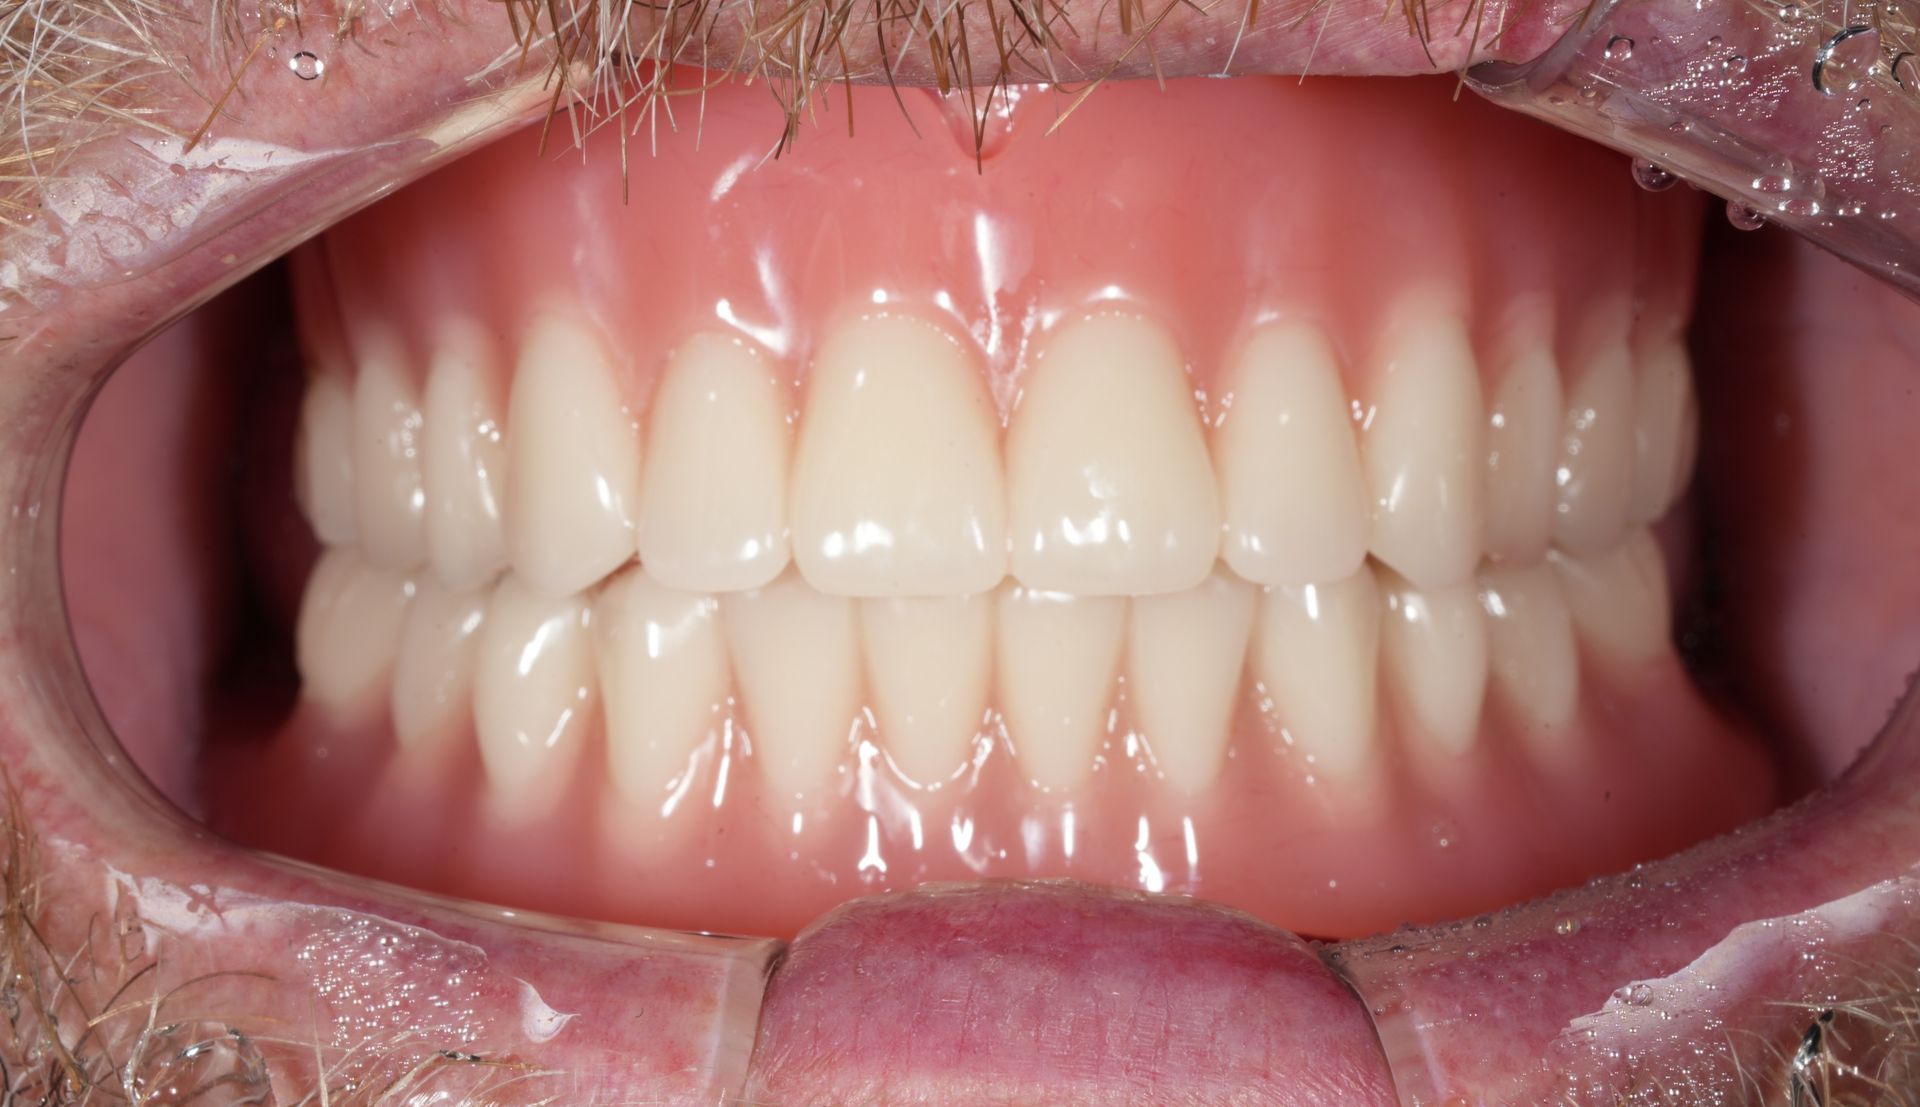

This image shows the completed overdenture in place.

In fully edentulous cases, the implant-supported overdenture structure allows the prosthesis to remain stable and resist movement,

providing significantly improved retention compared with conventional dentures.

Because an overdenture is supported by a locator system connected to implants,

it provides significantly better retention than conventional full dentures that rely solely on the gums.

This structure helps reduce movement during everyday chewing and speaking, improving overall function and comfort.

In addition, because the overdenture is removable, oral hygiene is easier to maintain,

and components such as retention caps can be replaced or the internal surface adjusted during regular check-ups.